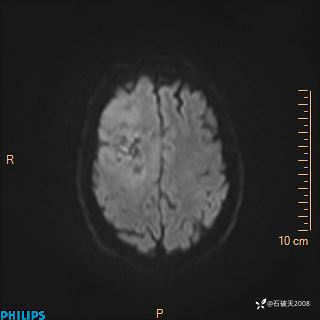

2024.2.21MR

DWI